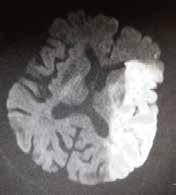

Rzadko stosowaną w codziennej praktyce klinicznej jest technika obrazowania czynnościowego (functional MRI – fMRI). Polega ona na detekcji zwiększenia utlenowania ośrodków w korze mózgu po zadziałaniu odpowiednich bodźców, np. wzrokowych, słuchowych czy ruchowych. Badanie ocenia zaburzenia czynności kory mózgowej, co niekiedy istotne jest w diagnostyce przedoperacyjnej guzów mózgu. Niekiedy w praktyce klinicznej w różnicowaniu uwidocznionych niejasnych co do charakteru zmian ogniskowych stosuje się spektroskopię rezonansu magnetycznego (magnetic resonance spectroscopy – MRS). Technika oparta jest na dyskretnych różnicach sygnału RM różnych związków chemicznych w tkance nerwowej, dzięki czemu uzyskuje się widma spektroskopowe określające stężenie podstawowych metabolitów. Najczęściej stosowana jest spektroskopia protonowa. Najistotniejszymi metabolitami w spektroskopii protonowej są: N-acetyloasparaginian, cholina, mleczany, kreatyna i mioinozytol. Stężenie metabolitów wraz z ich wzajemnym stosunkiem ulega zmianie w różnych patologiach, zwłaszcza w guzach. Na rycinie 1.35 przedstawiono nadostrą fazę udaru niedokrwiennego.

Rycina 1.35. Nadostra faza udaru niedokrwiennego. Badanie RM w sekwencji DWI uwidacznia restrykcję dyfuzji w lewej półkuli mózgu w zakresie unaczynienia gałęzi tętnicy środkowej mózgu lewej.